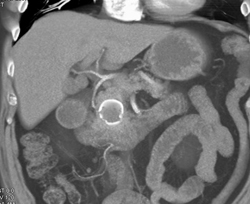

Pseudocyst